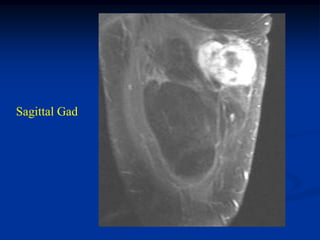

Case #298.1   Hemangioma Ankle                Sag Gad

Case #298.1

15 year male with tender

mass lateral side of forefoot

for many years

Sag T-1

T-2

Hemangioma Case #298.1 15 yearmale with tender mass lateral side of forefoot for many years